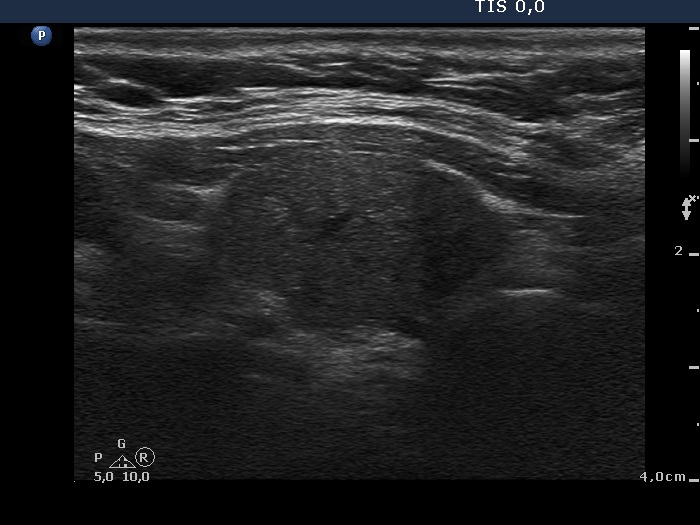

The borders of the nodule - case 1115

Five years after the surgery (ultrasonographic picture 2)

Right lobe, longitudinal scan. The upper part of the thyroid (left in the image) is more inhomogeneous while the lower three fourth is more hypoechogenic.